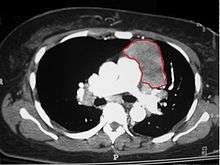

When a thymoma is suspected, a CT/CAT scan is generally performed to estimate the size and extent of the tumor, and the lesion is sampled with a CT-guided needle biopsy. Increased vascular enhancement on CT scans can be indicative of malignancy, as can be pleural deposits.[1] Limited biopsies are associated with a very small risk of pneumomediastinum or mediastinitis and an even-lower risk of damaging the heart or large blood vessels. Sometimes thymoma metastasize for instance to the abdomen.[3]

The diagnosis is made via histologic examination by a pathologist, after obtaining a tissue sample of the mass. Final tumor classification and staging is accomplished pathologically after formal surgical removal of the thymic tumor